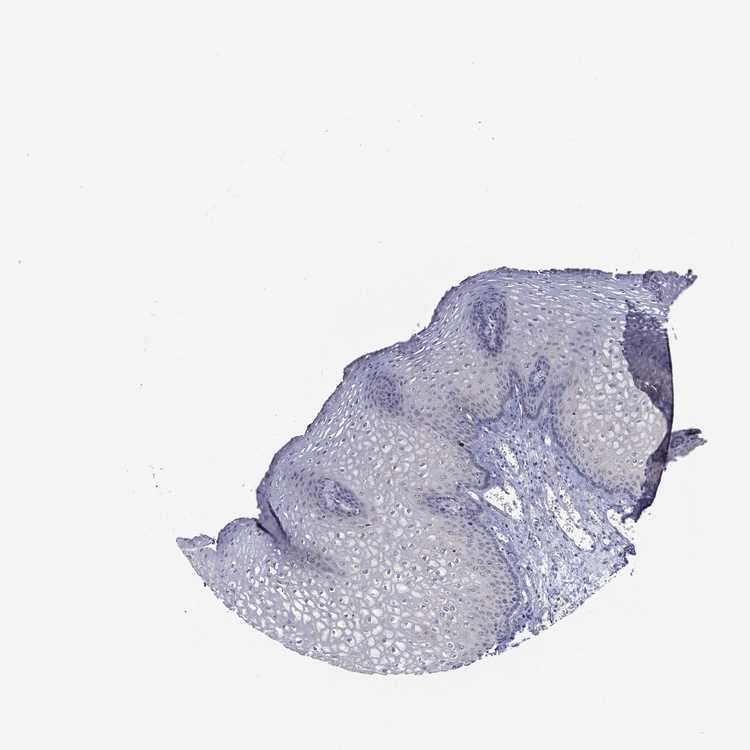

ESOPHAGUS - Antibody stainingi

Antibody staining in the annotated cell types in the current human tissue is reported as not detected, low, medium, or high, based on conventional immunohistochemistry profiling in selected tissues. This score is based on the combination of the staining intensity and fraction of stained cells.

Each image is clickable and will lead to virtual microscopy that enables deeper exploration of all samples and also displays staining intensity scores, fraction scores and subcellular localization as well as patient and tissue information for each sample.

Antibody HPA055421

Squamous epithelial cells Medium